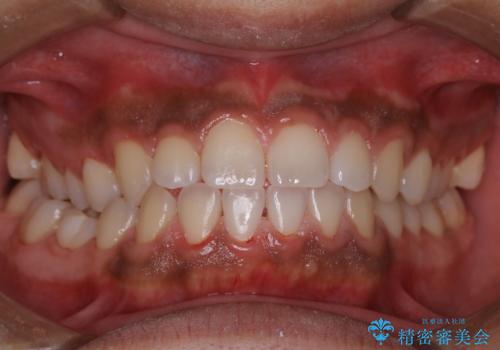

- 10年ぶりに歯科医院に来院された方です。クリーニングは人生で初めてとのことでした。

全体的に着色と汚れの量が多いため、PMTC60分コースで行いました。

歯石や着色、古くから蓄積した汚れは日常の歯ブラシではとることが出来ません。

歯科医院にて専門的に行うクリーニング(PMTC)を定期的に行うことがとても重要です。